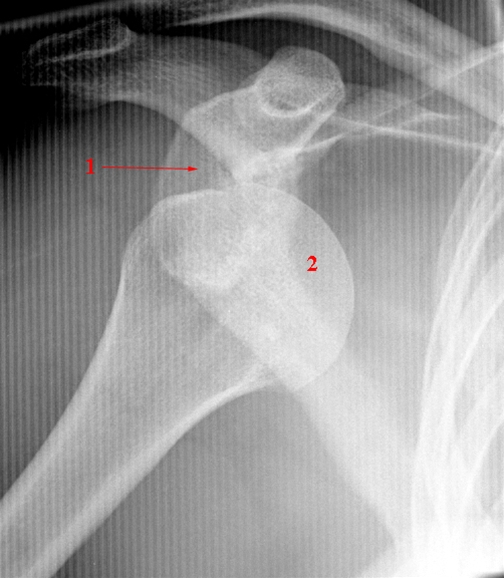

Skulderleds-luksation, røntgen

Glenohumeral luksation: Caput humeri Ledhoved (2) er lukseret anteriort og medialt cavitas glenoidalis (ledskålen) (1).